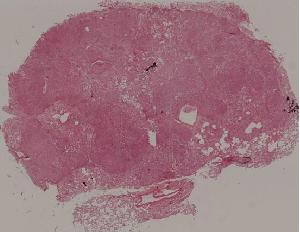

96.肺曲菌病